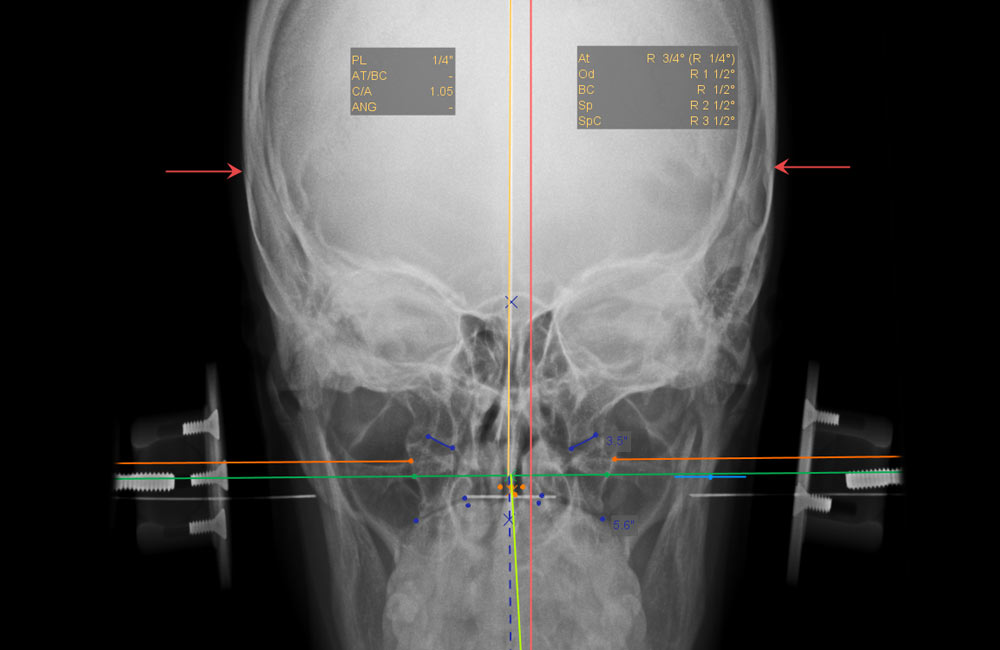

Atlas Plane Line and Atlas Check Line

NUCCA: Atlas Plane Line and Atlas Check Line